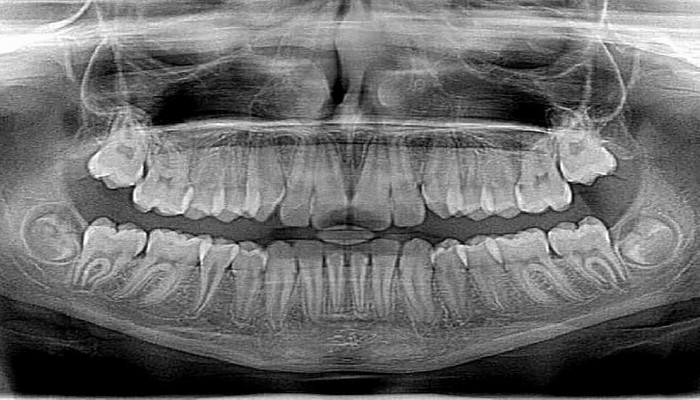

Рентгенография полости рта может выявить хроническое заболевание коронарной артерии

Кальциноз сонной артерии – признак прогрессирующего атеросклероза, который может быть связан с хронической коронарной недостаточность (КН) и может привести к смерти. Такой кальциноз можно увидеть при обычной панорамной рентгенографии полости рта.Kак сообщает Ens.az со ссылкой на Med2.ru

«Инфекции полости рта довольно распространены, но они часто являются латентными и обнаруживаются только при рентгенографии. Рентгенограммы всей челюсти, проведенные в сочетании со стоматологической помощью, могут выявить риск сердечно-сосудистых заболеваний. Если на рентгенограмме виден кальциноз сонной артерии, пациента необходимо направить на дальнейшие обследования», - рассказывает доцент Пиркко Пуссинен из Хельсинкского университета.